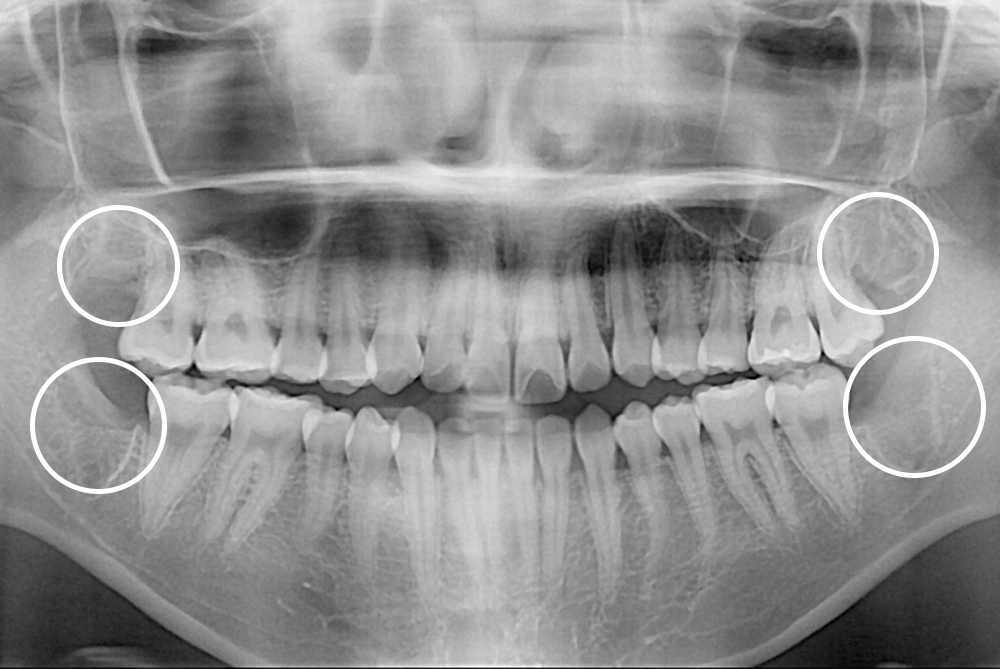

치료후 : 2021-06-05

세종치과는 구강악안면외과학 박사이신 원장님이 발치하는 치과입니다.